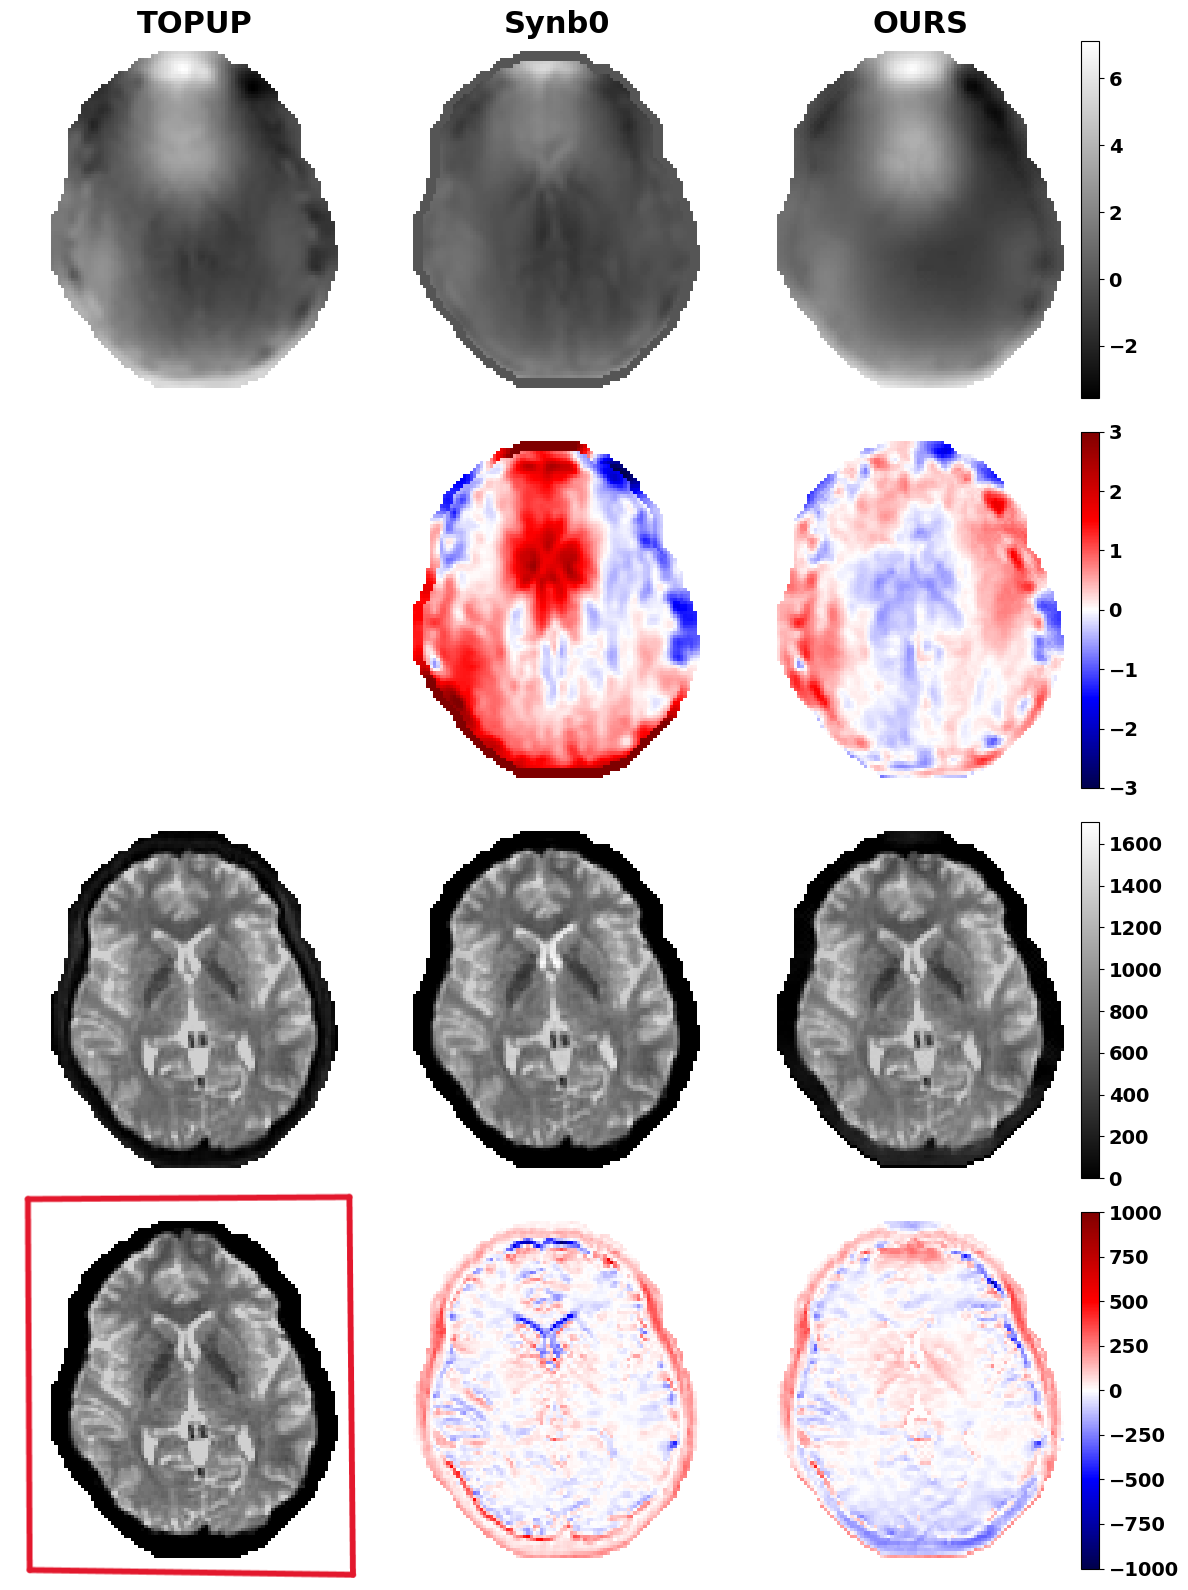

Figure 2 showcases the results of the proposed method, including the predicted VDMs and corrected b0 images, compared to those generated by and Synb0. While typically achieves the best anatomical alignment, thanks to its use of both blip-up and blip-down acquisitions, it cannot be applied when only a single phase-encoded image is available. Synb0 often under or overestimates broad distortion patterns. By contrast, our network learns a more accurate displacement map from a single input image. These results suggest that our approach can deliver near– quality with a single input image, making it a versatile alternative in data-limited scenarios.

We also compared each method’s MI against the T1w image using paired t-test (you can see the results in Figure 3). Under the paired t-test, achieves the highest median MI and outperforms Synb0 as well as our method, whereas the gap between Synb0 and ours does not reach significance. These statistics show that our approach achieves anatomical alignment on par with Synb0 and nearly as good as , despite using only one encoding direction.

Using the gradient loss term. Next, we remove the gradient-based term on the predicted VDMs to understand its impact on the final correction. As reported in the bottom half of Table 2, removing the gradient term leads to a modest increase in VDM and b0 RMSE, a slight raise in MI with the T1w image. Both sets of VDMs, whether trained with or without the gradient penalty, remain smoother than the reference as shown in Figure 4, suggesting our network’s architecture already favors smooth displacement estimates. Therefore, the extra gradient-loss term delivers only a small numeric gain in RMSE but does not yield any clear boost in anatomical alignment.